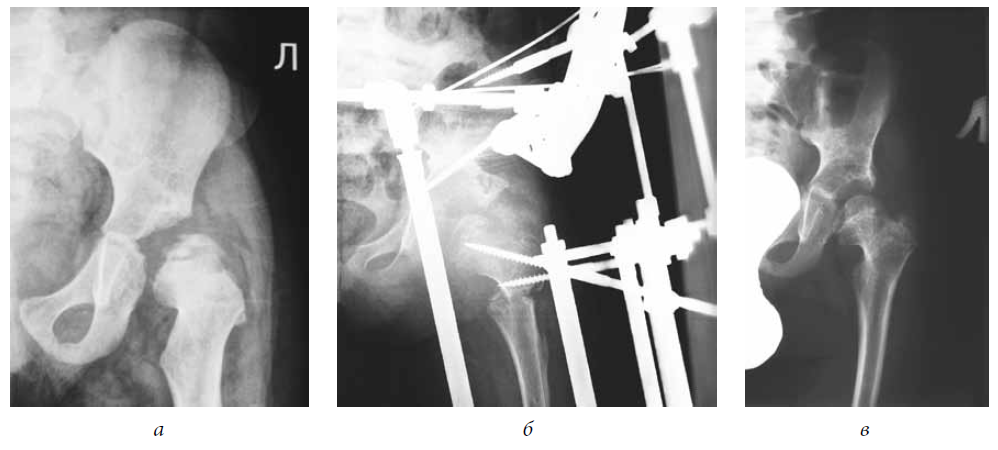

There were no cases among the joints examined that presented with an excellent outcome. Good results were noted only when performing extra-articular interventions (see Table 2). In general, positive outcomes were observed in 94% (Figs. 1–3).

Fig. 3. Patient F., 4 years old, with a diagnosis of congenital dislocation of the right hip, degree III of dislocation, and degree IV Perthes disease: a — frontal radiograph of the hip joint before treatment; b — frontal radiograph of the hip joint during treatment (after performing an open reduction of the dislocation, shortening correcting osteotomy of the hip, osteotomy of the iliac bone, tunneling of the femoral neck and head, hardware decompression of the articulation); c — frontal radiograph of the hip joint 4 years after treatment